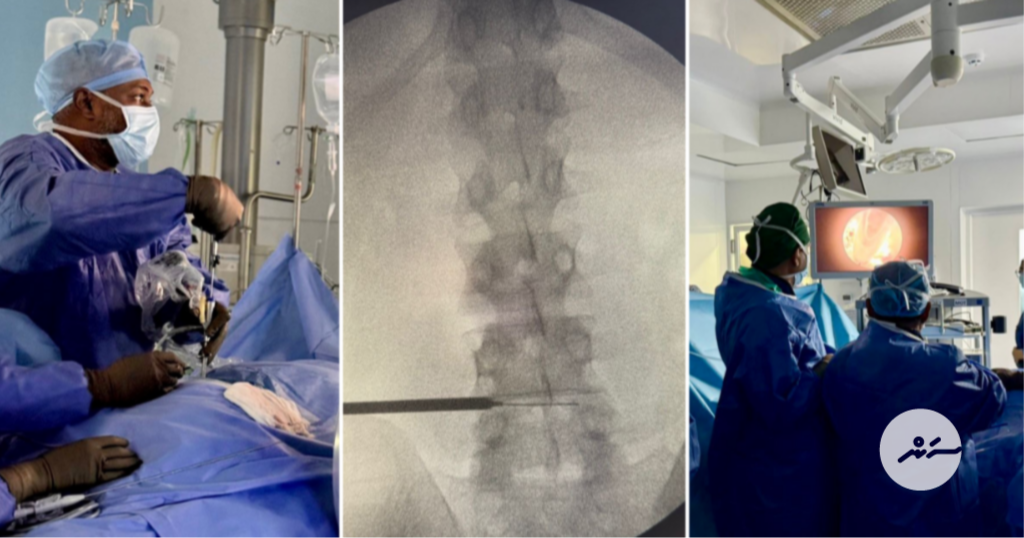

މައިބަދައަށް ކެމެރާ ލައްވައިގެން ކުރާ އޮޕަރޭޝަން އައިޖީއެމްއެޗްގައި ކުރަނީ-- ފޮޓޯ: އައިޖީއެމްއެޗް

މި އޮޕަރޭޝަން ކުރުމަށް ޑޮކްޓަރުން ކުޑަ ހޮޅިއެއްގެ ތެރެއިން ކެމެރާއާއި އޮޕަރޭޝަނަށް ބޭނުންވާ އާލާތްތައް ވައްދާނީ މައިބަދައާއި ދިމާލުން ކުޑަ ލޯވަޅެއް ތޮރުފައިގެންނެވެ. އެއަށް ފަހު، ބުރަކައްޓަށް ދިމާވެފައިވާ މައްސަލަ ހައްލުކުރަނީއެވެ.

އާންމުކޮށް ފަޅައިގެން ކުރާ އޮޕަރޭޝަންތަކާ ހިލާފަށް މި ގޮތަށް ނުފަޅާ ކުރާ އޮޕަރޭޝަންތަކުގެ ފައިދާ ވަރަށް ބޮޑެވެ. އެއީ، އޮޕަރޭޝަނަށް ފަހު ވާ ތަދުކުޑަވުމާއި އަވަހަށް ރަނގަޅުވުމުގެ އިތުރުން ފާރުގަނޑުގެ ލަކުނު ކުޑަވުމެވެ. އަދި ފަޅައިގެން ކުރާ އޮޕަރޭޝަނަށް ވުރެ މި ގޮތަށް ކުރާ އޮޕަރޭޝަންތަކުން ހޮސްޕިޓަލުން ދޫކޮށްލާ މުއްދަތު ވެސް ކުޑަވެއެވެ.